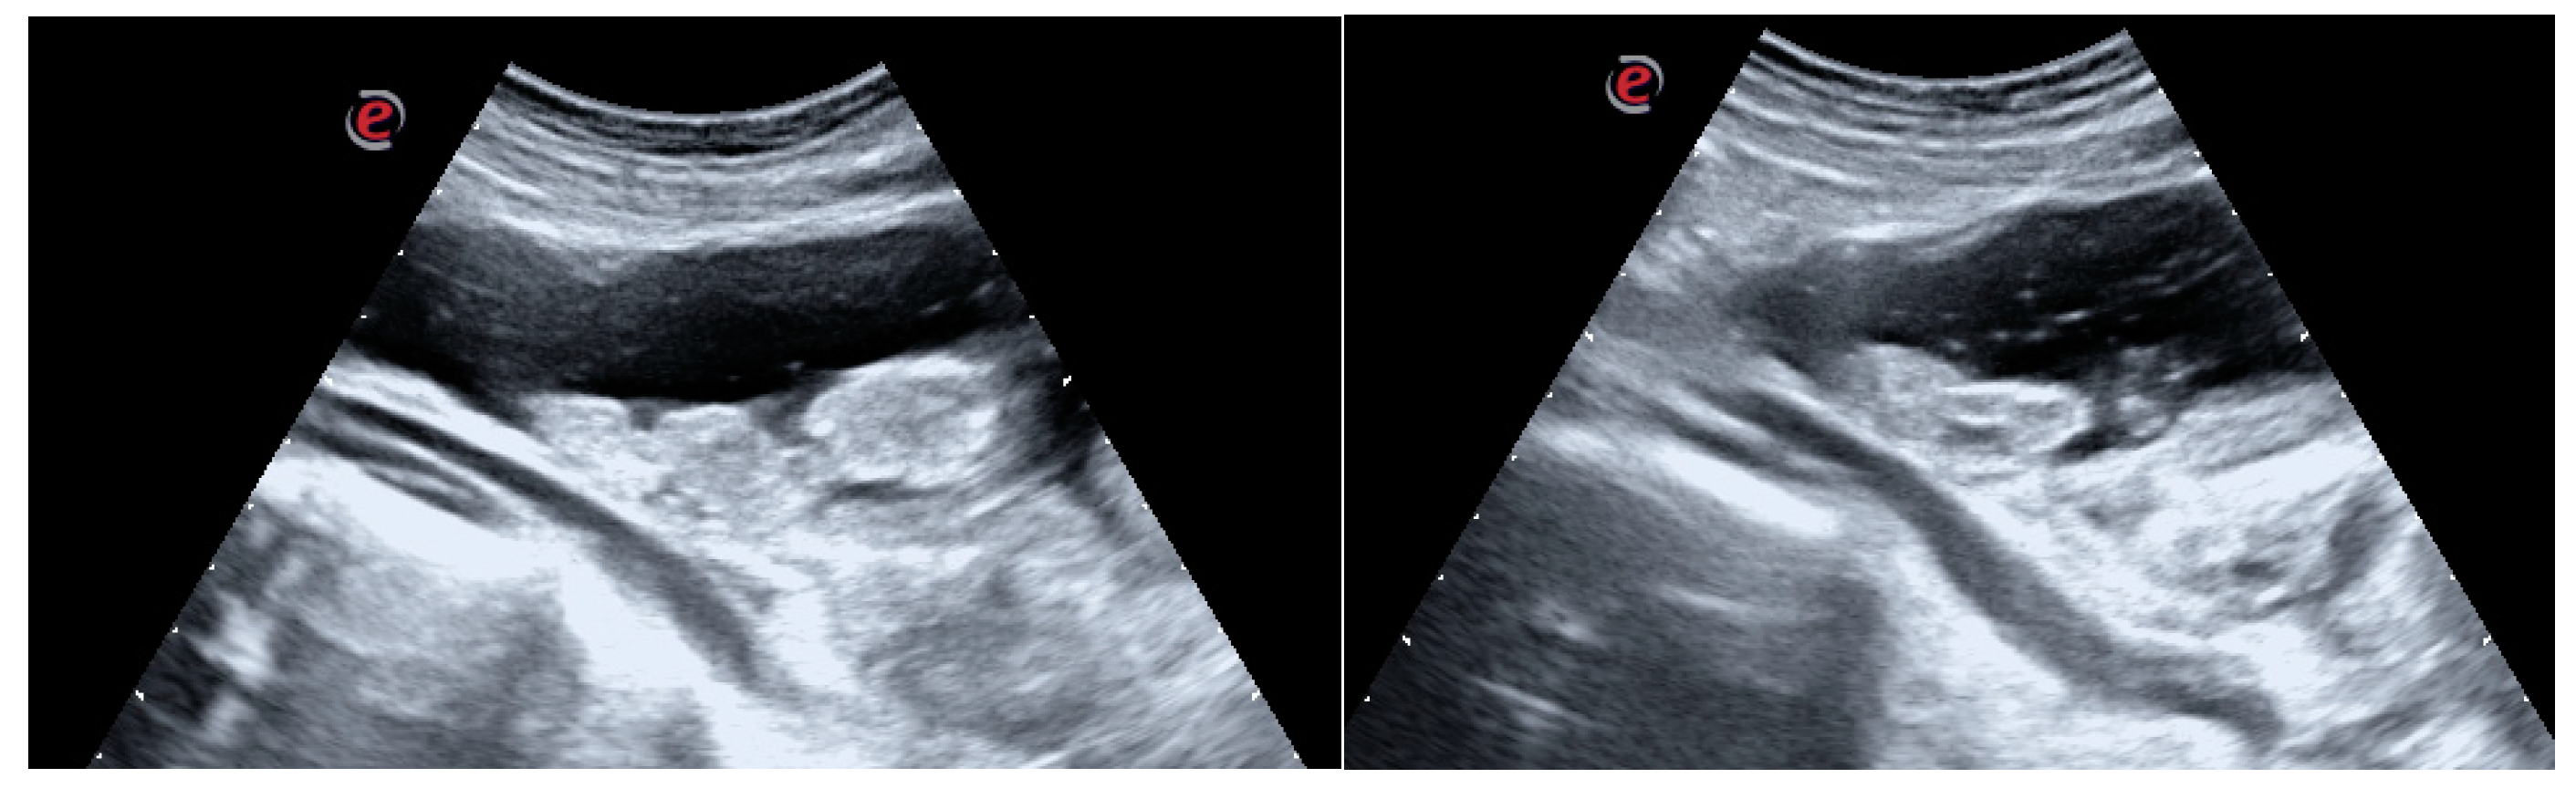

Abdominal US showed a large clot filling the bladder, varying position depending on the patient decubitus. The clot had a 10 centimeters diameter as a main projection (Figure 1a,b).

Figure 1. (a-b) Diagnostic Assessment: US images of the large clot occupying the entire bladder lumen.